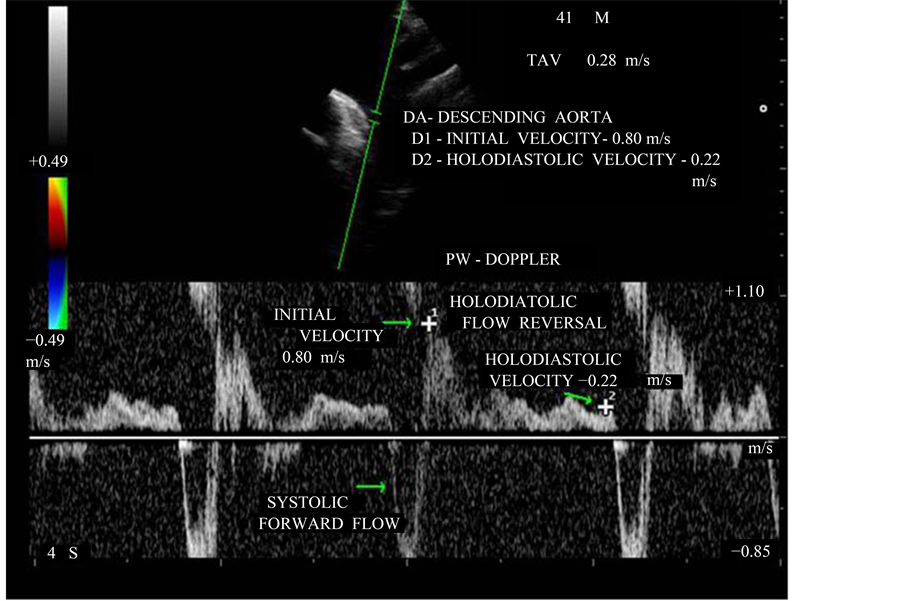

Figure 17. PW doppler showing the “holodiastolic flow reversal” in the descending aorta-supra- sternal notch view).

3.9. Aortic Diastolic Flow Reversal

A brief diastolic flow reversal in aorta is normal and it is best recorded at aortic isthmus level in the upper descending aorta by pulsed-wave doppler. With increasing aortic regurgitant, both the duration and velocity of reversal increase [53] . Therefore, a holodiastolic reversal as shown in Figure 17 is usually a more specific sign of at least moderate aortic regurgitation. Retrograde flow measured by pulsed-wave Doppler immediately after subclavian artery and if end diastolic flow velocity is <18 cm/s = does not indicate hemodynamically significant AR (grade I and II), >18 cm/s = indicate hemodynamically significant AR (grade III and IV). In severe cases, the initial diastolic flow velocity is >0.6 m/s and TVI backflow signal >15 cm. In this patient, the initial diastolic flow velocity is 0.80 m/s and end diastolic velocity 0.22 m/s correlate with severe aortic regurgitation. Holodiastolic flow reversal can be used to assess the aortic regurgitation following TAVR (Transcatheter aortic valve replacement-paravalvular leak).